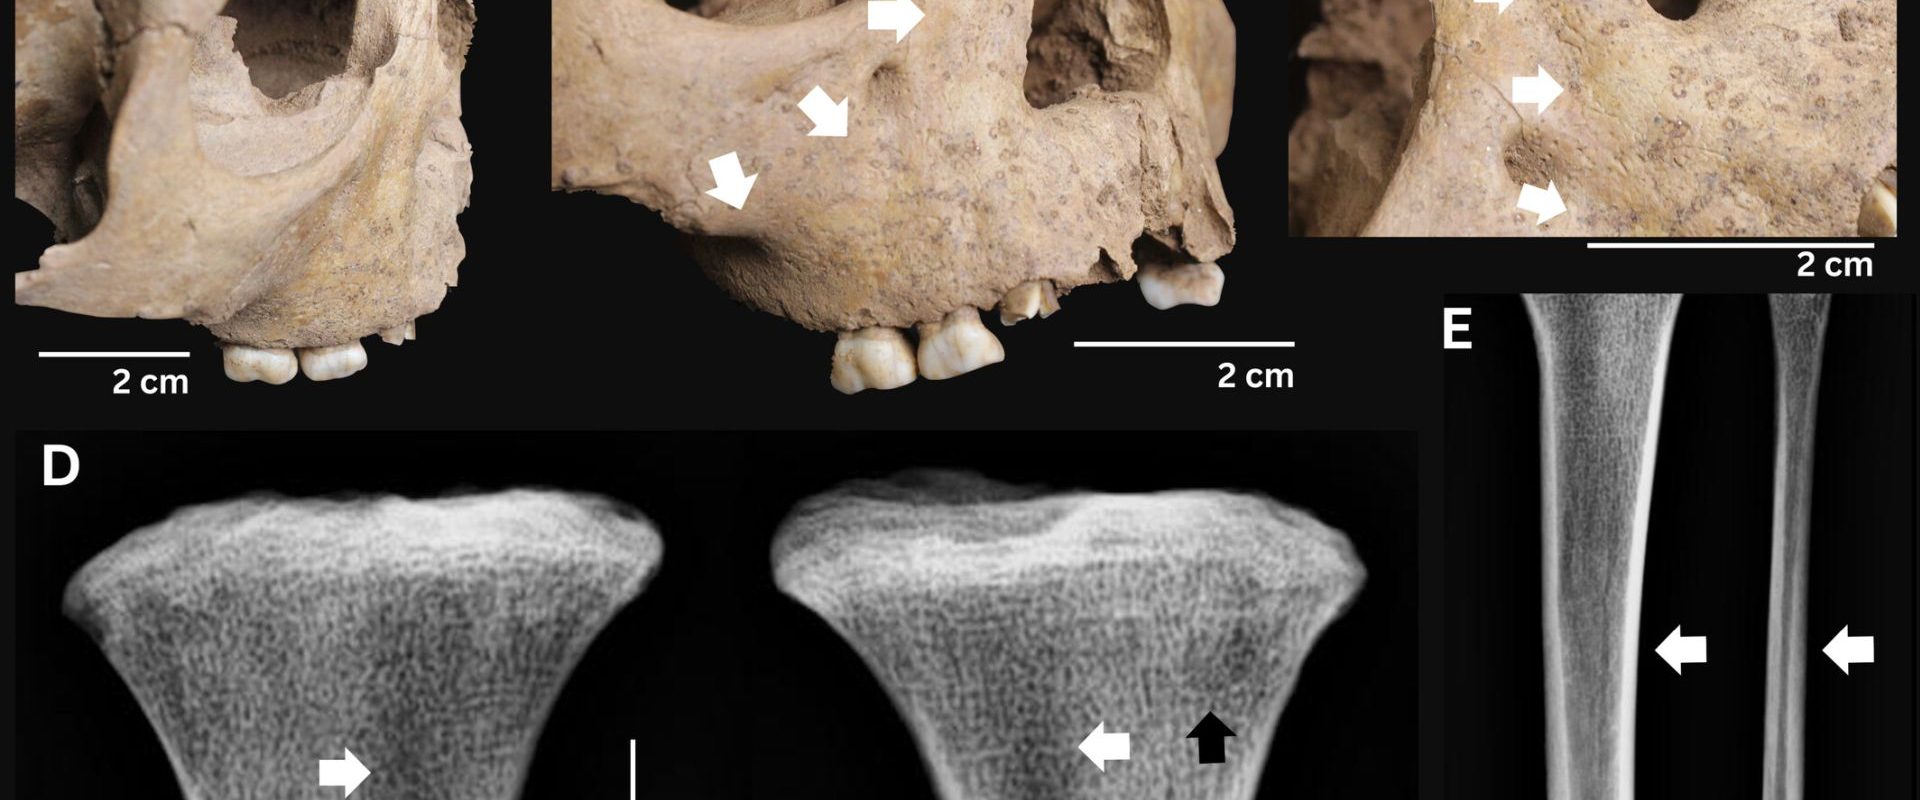

Descoperirea a fost realizată în urma analizei scheletelor provenite din Epoca de Piatră, mai exact din două situri neolitice din Vietnam, datând de acum aproximativ 4.100-3.300 de ani. Cercetătorii au identificat urme specifice ale bolii pe dinții a trei copii, semne care sugerează o treponematoză congenitală. Această boală este cauzată de bacteria Treponema pallidum, din aceeași familie cu sifilisul, bejelul și framboesia.

Un aspect crucial al acestei descoperiri este că boala a fost identificată în rândul copiilor, sugerând o transmitere congenitală, de la mamă la făt. Anterior, se credea că doar sifilisul se transmite în acest mod. Această informație zdruncină teoria conform căreia sifilisul și-ar fi avut originea în Americi, teorie susținută de descoperiri anterioare. „Noua noastră cercetare schimbă complet paradigma. Transmiterea congenitală nu este exclusivă la sifilis”, a declarat unul dintre cercetătorii implicați în studiu.

Studiul a examinat 304 indivizi din 16 situri arheologice din Vietnam. Din totalul analizei, trei copii au prezentat semne clare ale bolii, cu dinți deformați, subdezvoltați sau cu aspectul specific de „roz de viermi”. Prezența cazurilor de treponematoză congenitală complică modelul de transmitere și pune sub semnul întrebării ipoteza „Columb”, care susține că boala a fost adusă în Europa din Lumea Nouă.